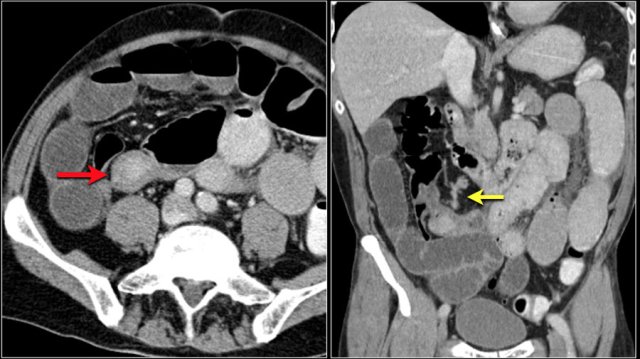

The images show a carcinoid tumor presenting as a hypervascular mass (red arrow) with desmoplastic reaction (yellow arrow).

Carcinoid tumors are slowly growing tumors that may go unrecognized for many years.

They start as small submucosal lesions (images).

As the carcinoid grows, thickening of the bowel wall occurs, leading eventually to extension outside the bowel wall.

Carcinoid tumors can cause an intense desmoplastic reaction with retraction of bowel loops and fibrosis, sometimes leading to bowel ischemia.